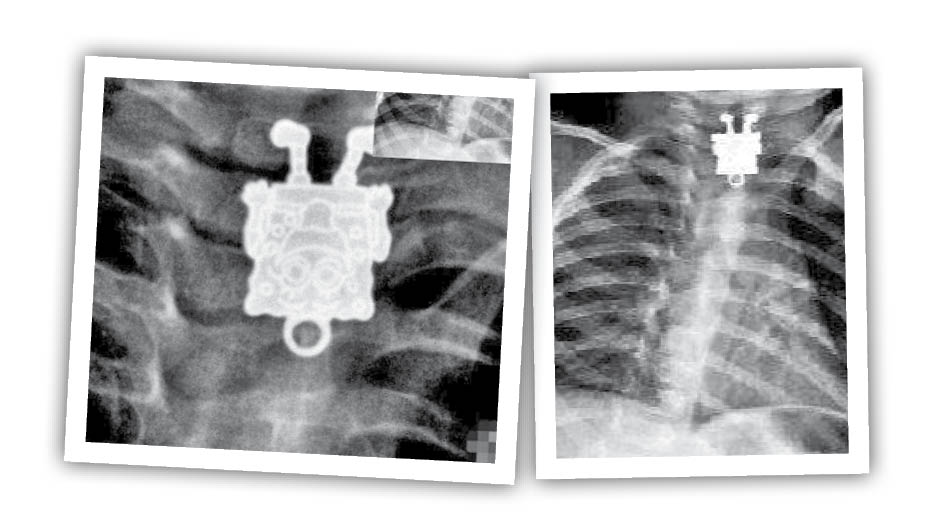

این تصویر رادیو گرافی یک کودک ۱۶ ماهه است که یک آویز باب اسفنجی را بلعیده و در گلوی او گیر کرده است. این اولین باری نیست که چنین تصاویری از رادیوگرافی کودکانی که جسمی را بلعیدهاند، منتشر میشود؛ کودکانی که اجسام سخت و عجیبی مثل سوزن، باتری، کلید و.... را خوردهاند و جسمشان به خطر افتاده است. در آخرین مورد کودکی با خوردن باتری، معلول جسمی شد که تحت درمان است. پس اگر کودکی در اطراف خود دارید مراقبت بیشتری از او داشته باشید تا گرفتار نشوید.